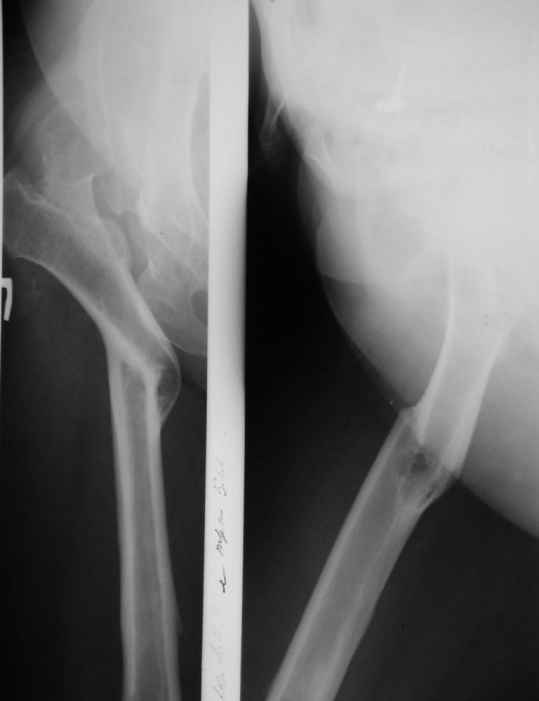

В прищепке случай 1999 года - эндопротезирование после операции Шанца

Илизарова. Возраст пациентки 45 Коррекция была в 17 лет.  А Рыков Хабаровск.

Пациентка 51 года обратилась с жалобами на выраженные боли в правом т/б

суставе. Болеет с детства. В возрасте 10 лет коррегирующая вальгизирующая

остеотомия вертельной области правой бедренной кости. В 2001 году тотальное

гибридное протезирование левого т/б сустава.

из возможных вариантов решения возможно коррегирующая варизирующая

остеотомия правой бедренной кости с дальнейшим тотальным протезированием

(механика?) с удлиненным бедренным компонентом.